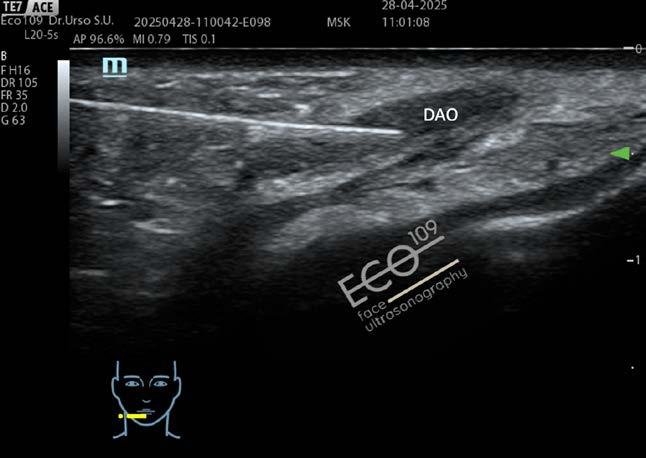

L’ecografia del volto nella Medicina Estetica avanzata